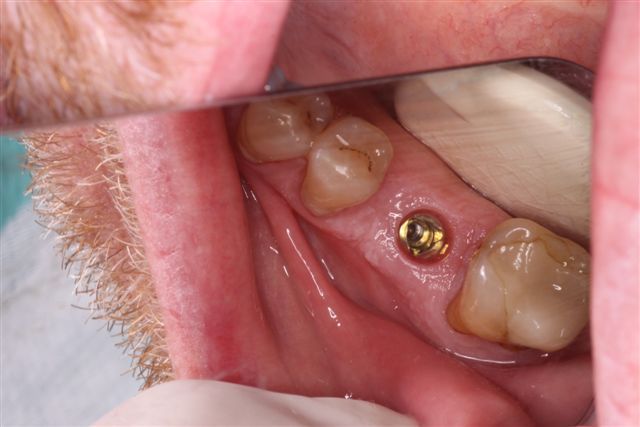

STEP 1 > Initial Implant Presentation with Healing Cap

STEP 2 > Show Impression Coping in Place